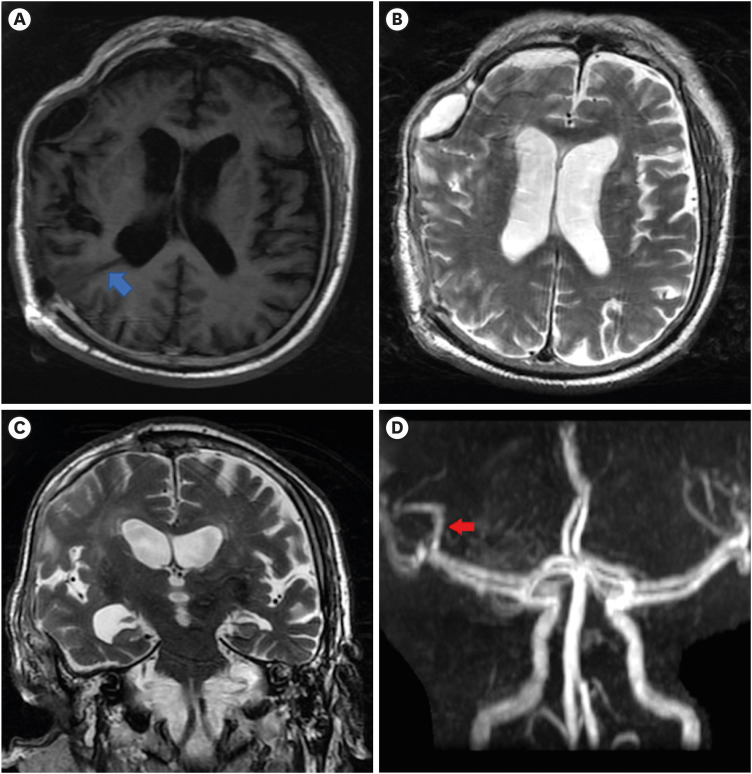

创伤后脑积水(PTH)是减压颅骨切除术后常见的并发症,通常表现为头痛、恶心、呕吐和乳头水肿等症状。在硬膜下血肿清除术后接受开颅手术的 PTH 患者中,颅外疝伴偏瘫是一种罕见的并发症。我们报告了一例在颅骨减压切除术后一个月内出现颅外疝的 PTH 患者。植入脑室腹腔分流术后,随着左侧大脑中动脉血流的恢复,左侧偏瘫得到明显改善,这在连续影像学检查中显而易见。临床医生在处理脑外伤患者时,血管损伤往往被颅内压增高所掩盖。精细的神经学和放射学检查以及及时的早期干预可为接受颅骨减压切除术的患者带来最佳治疗效果。

Post-traumatic hydrocephalus (PTH) is a commonly encountered complication following decompressive craniectomy, and is usually characterized by symptoms including headache, nausea, vomiting, and papilledema. Extracranial herniation accompanied by hemiplegia is a rare complication in patients with PTH who underwent craniectomy after subdural hematoma removal. We report a case of PTH that presented with extracranial herniation within one month of decompressive craniectomy. Following ventriculoperitoneal shunt implantation, left hemiplegia improved dramatically with restoration of the left middle cerebral artery blood flow, which was evident on serial imaging. Vascular compromise is often overshadowed by increased intracranial pressure when clinicians are dealing with traumatic brain injury patients. Delicate neurological and radiological examinations and prompt early interventions could lead to optimal outcomes in patients receiving decompressive craniectomy.